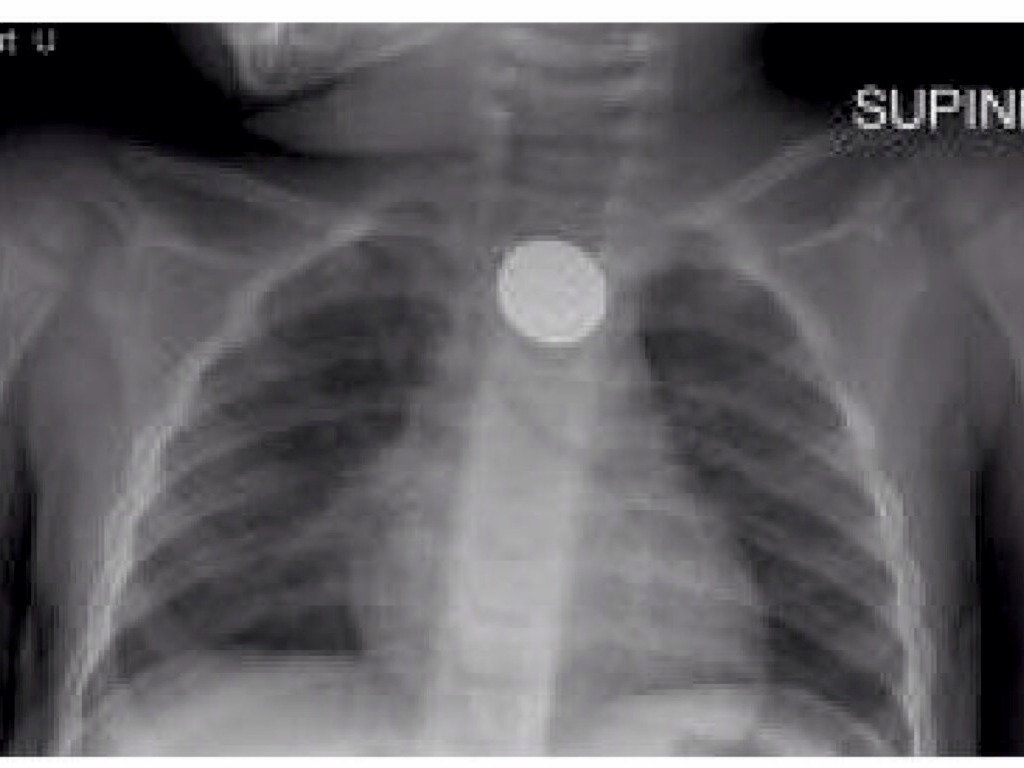

This guy is swallowing a _________?